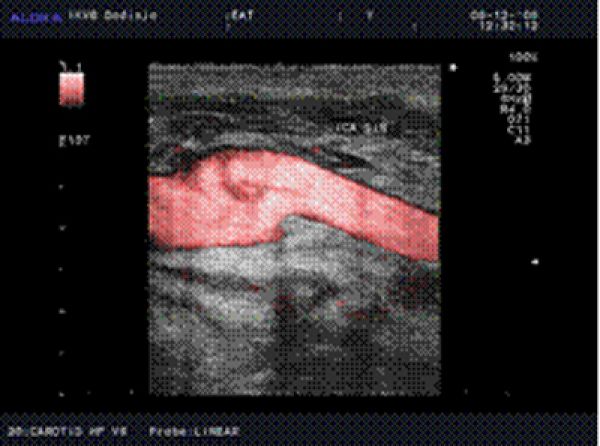

Kontrolna Duplex-ultrasonografija nakon everzione endarterektomije. Uredan nalaz sa glatkim unutrašnjim slojem, bez znakova turbulencije na longitudinalnom snimku.